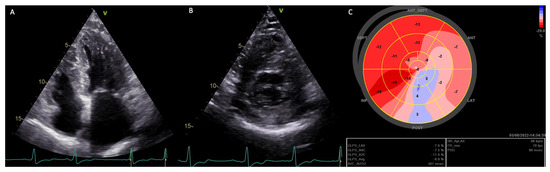

In analyzing patients with classic variants, common features were severe cardiac hypertrophy, reduced GLS, and increased MD. Specific cases among females include a patient (E341X) who had severe cardiac hypertrophy and passed away due to acute heart failure. Another patient (R220X) exhibited severe LVH (apical hypertrophy) and recurring AF (Figure 5).

Figure 5. Echo images of a female AFD patient with LVH carrier of a pathogenic mutation linked to a classic form (R220X). Panel (A)—apical four chambers view; panel (B)—parasternal short axis view; panel (C)—global longitudinal strain (bull’s eye), mostly impaired in the inferolateral segments. LV-GLS average: −8.8%, frame/min 70, HR 66 bpm, MD 88 ms.